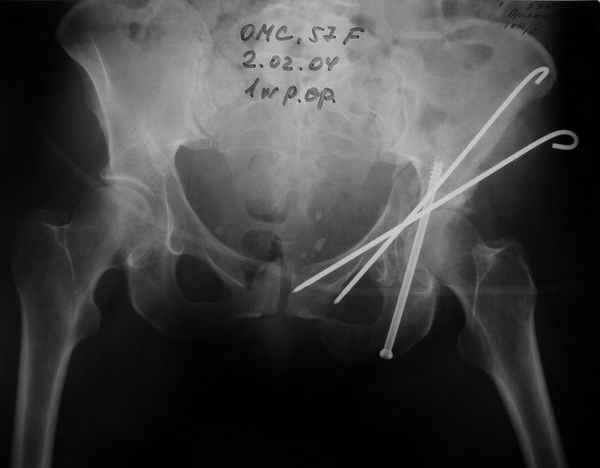

Anatoly F Lazarev 03 Сентябрь 2004, 22:18

Женя! Класный перелом. Отлично репонируется изнутри таза, но лучше фиксированть сзади. Классический перелом для двустороннего доступа.

Однако есть альтернатива. Репозиция из подвздошного доступа тазовыми щипцами с разнодлинными браншами или тазовым пистолетом, а фиксация задней колонны через седалищный бугор или тазрвыми винтами 4,5 или каннюлированными 6,5 или 7,3. По-моему я посылал на ортофорум такой снимок, когда жаловался на ишемический неврит седалищного нерва через сутки после операции. Не забудь про шейку бедра - мне кажется будет хорош длинный PFN любой фирмы, какую ты найдешь, а нет так UFN + miss a nail, как это здорово делают мои земляки - Ебурбуки. Пока.

Anatoly F Lazarev 03 Сентябрь 2004, 22:39

Высылаю пример еще одного случая, остеосинтез пластиной из подвздошного доступа.